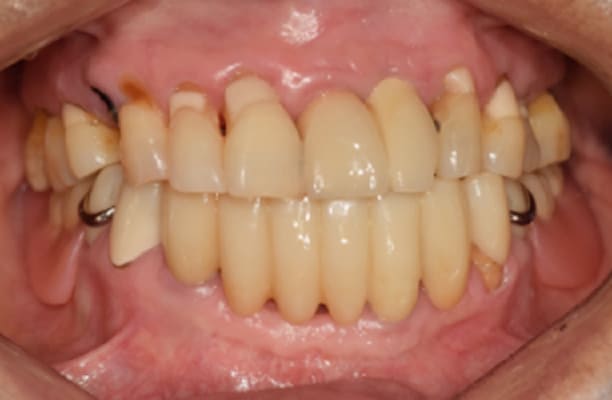

-

术前 -

术后